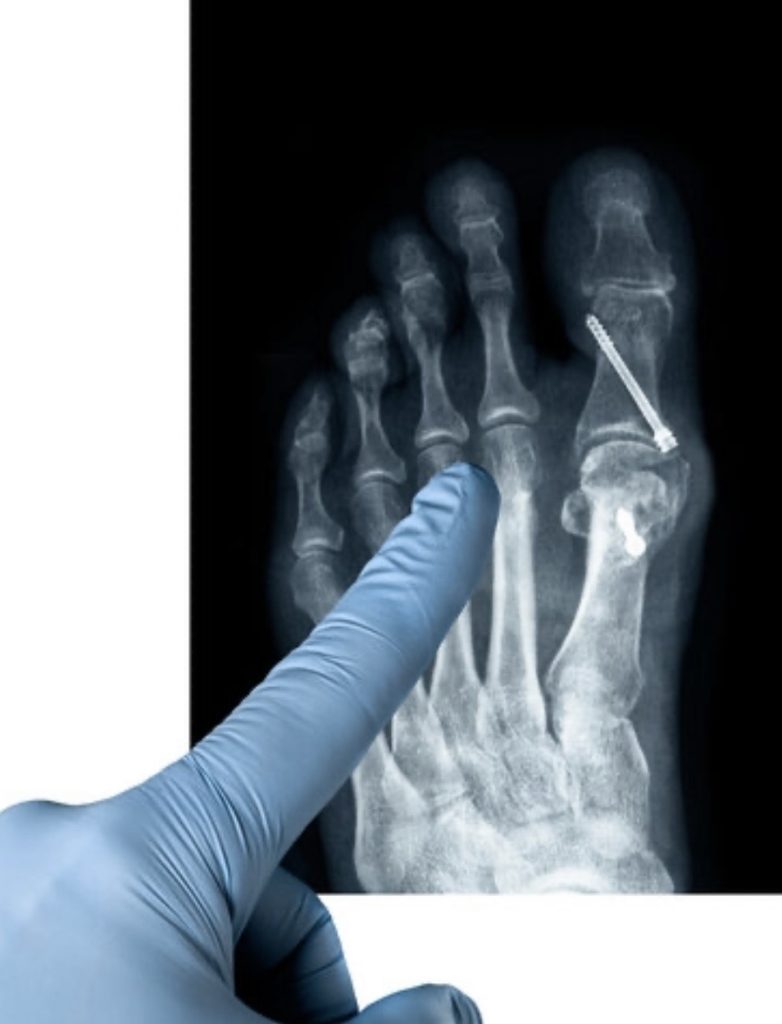

Cirugía de juanetes en Aranjuez

El objetivo quirúrgico es corregir la desviación y restaurar la alineación.

Objetivos de la intervención

- Eliminar la prominencia ósea

- Corregir la desviación del dedo

- Mejorar la biomecánica del pie

- Corregir deformidades asociadas

Técnicas quirúrgicas disponibles

Cada caso requiere una planificación específica.

Opciones utilizadas

- Cirugía mínimamente invasiva

- Técnicas abiertas convencionales

La elección depende del grado de deformidad y de la anatomía de cada paciente.